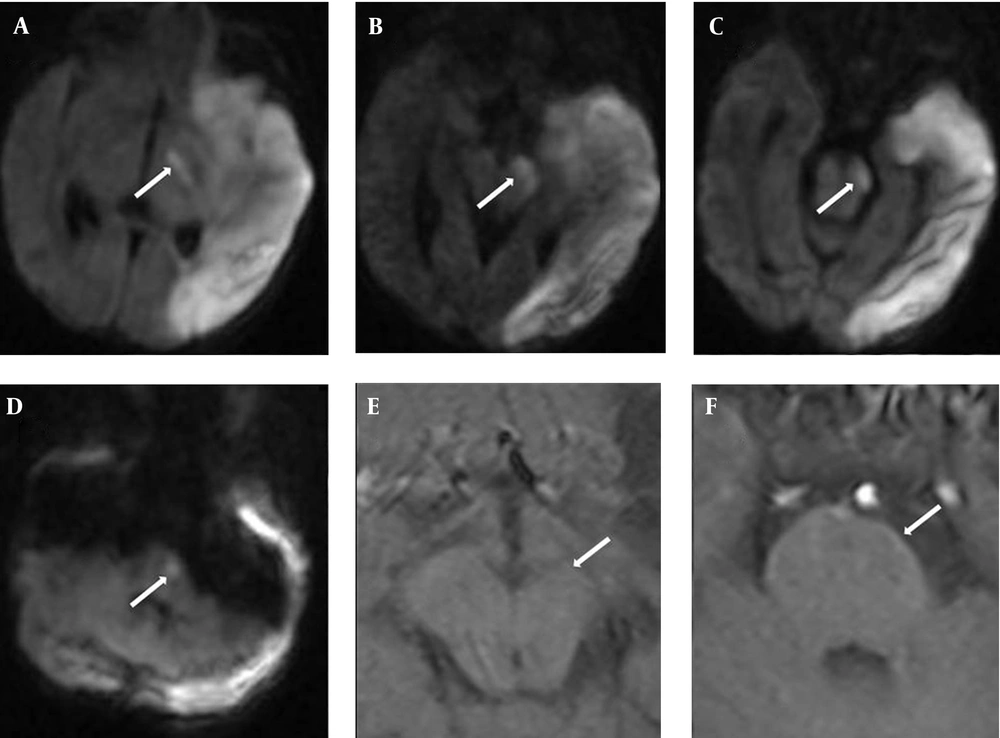

A 1-day-old male neonate was born at 37 weeks’ gestation via cesarean section due to breech presentation. He weighed 2225 g (10-25th percentile), was 48 cm in length (50-75th percentile), and had a head circumference of 33 cm (50th percentile). Apgar scores were 6 and 8 at 1 and 5 minutes, respectively. Maternal hypertension developed 2 weeks before delivery and was treated. After birth, delayed initial crying and cyanosis were noted. Resuscitation was done and the infant was hospitalized for observation. On physical examination, weak sucking and breath holding while crying were noted. Cranial ultrasound on day 3 revealed very mild increased echogenicity over the left thalamus, basal ganglia and periventricular area with ventricular compression (Figure 1). Decreased right upper and lower limb movements were observed on day 4 of life. Repeated cranial ultrasound on day 5 of life revealed more echogenicity over left thalamus, basal ganglia and periventricular area (Figure 1). For further evaluation, magnetic resonance imaging (MRI) and magnetic resonance angiography (MRA) with diffusion-weighted imaging (DWI) were performed on day 5 of life. The T2-weighted brain MRI (T2WI) showed high signal intensity (SI) over the left fronto-parieto-occipital cortical and white matter areas. MRA showed flow reduction over the left MCA branch (Figure 1). Middle cerebral artery (MCA) infarction was diagnosed. Pre-Wallerian degeneration was also noted on DWI, with high SI over the left posterior limb of internal capsule (PLIC), cerebral peduncle and basis pontis (Figure 2).

The patient developed spastic hemiplegia in the following months. MRI performed when he was 8 months of age revealed multicystic encephalomalacia and Wallerian degeneration (Figures 1, 2).

Early Wallerian degeneration (or Pre-Wallerian degeneration), first described in infants by Mazumdar et al. is an acute corticospinal tract injury preceding Wallerian degeneration (4). Early Wallerian degeneration can be detected within the early days of acute AIS, manifesting as increased SI in the ipsilateral descending corticospinal tract (PLIC, cerebral peduncle, basis pontis, and medullary pyramid) on DWI (5). It has been shown that a neonatal descending corticospinal tract (DSCT) DWI signal abnormalities, including the percentage of cerebral peduncle affected, the length of DCST affected, and the relative volume of the DWI DCST lesion, are predictive of motor outcome (5). Similar findings were found on childhood and adult stroke (6, 7). In this index case, early Wallerian degeneration with subsequent Wallerian degeneration were noted (Figure 2), which correlated with the poor motor outcome.

DWI findings on day 5 of Life with DSCT Pre-wallerian degeneration over the PLIC (A), Peduncle (B, C), and basis pontis (D). T1WI performed when the infant was 8 months of age showed volume loss over the left cerebral peduncle (E) and basis pontis (F), compatible with Wallerian degeneration (arrow).